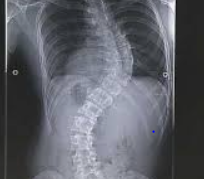

척추측만증, 일명 'Scoliosis',는 척추가 옆으로 휘어지는 상태를 말합니다. 이 상태는 척추가 정상적인 'S' 또는 'C' 모양의 곡선을 형성하게 되며, 이로 인해 다양한 건강 문제를 초래할 수 있습니다. 척추측만증의 원인은 다양하며, 여러 연구를 통해 여러 가설이 제시되었습니다.

척추측만증, 일명 '측만증'은 척추가 옆으로 휘어지는 질환으로, 정상적인 척추의 모양에서 벗어난 상태를 말합니다. 이 질환은 척추가 'S' 형태나 'C' 형태로 변형되는 것이 특징이며, 다양한 증상을 동반할 수 있습니다. 척추측만증의 증상은 개인마다 다르게 나타나며, 때로는 눈에 띄지 않을 정도로 경미할 수도 있습니다. 그러나 일부 환자에서는 통증, 신체의 불균형, 호흡 곤란 등의 심각한 증상을 경험할 수 있습니다.

척추측만증은 엑스레이나 자기 공명 영상(MRI) 검사를 통해 진단할 수 있으며, 척추의 만곡이 10도 이상일 때 측만증으로 진단됩니다. 치료 방법은 증상의 정도와 환자의 나이, 만곡의 진행 속도 등에 따라 달라질 수 있습니다. 경미한 경우에는 정기적인 관찰과 운동 요법으로 관리할 수 있으며, 심한 경우에는 보조기 착용이나 수술적 치료가 필요할 수 있습니다.

1. 관찰: 경미한 척추측만증의 경우, 특별한 치료 없이 정기적인 의사 상담과 X-선 검사로 진행 상황을 추적하는 것이 충분할 수 있습니다. 이는 만곡이 20도 미만일 때 주로 고려됩니다.

2. 보조기 착용: 만곡이 20도에서 40도 사이이며, 아직 성장 기간이 남아 있는 환자에게는 보조기를 착용하여 만곡의 진행을 막고 교정하는 방법이 사용됩니다. 보조기는 척추의 균형을 유지하고 추가적인 만곡을 방지하는 데 도움을 줄 수 있습니다.

3. 수술적 치료: 만곡이 심하거나 보조기 착용으로 개선되지 않는 경우, 수술적 치료가 필요할 수 있습니다. 수술은 척추의 만곡을 교정하고 고정시키는 것을 목표로 하며, 이는 주로 40도 이상의 만곡에 적용됩니다.